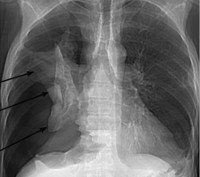

Пневмоторакс (от -греч. πνεῦμα - дуновение, воздух и θώραξ - грудь) - скопление воздуха или газов в плевральной полости. Он может возникнуть спонтанно у людей без хронических заболеваний лёгких («первичный»), а также у лиц с заболеваниями лёгких («вторичный»). Многие пневмотораксы возникают после травмы грудной клетки или как осложнение лечения.

Симптомы пневмоторакса определяются размером и скоростью поступления воздуха в плевральную полость; к ним относятся в большинстве случаев боль в груди и затруднённое дыхание. Диагноз может быть выставлен при физикальном обследовании в некоторых случаях, но иногда необходима рентгенография грудной клетки или компьютерная томография (КТ). В некоторых ситуациях, пневмоторакс приводит к тяжёлой нехватке кислорода и снижению кровяного давления, прогрессируя в остановку сердца при отсутствии лечения; такое состояние называют напряжённый пневмоторакс.